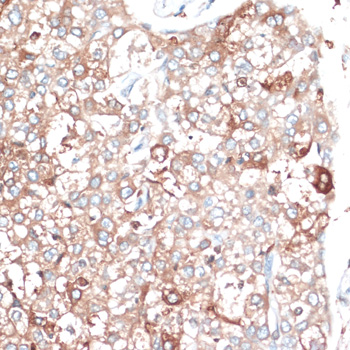

Immunohistochemistry of paraffin-embedded human liver cancer using SLAMF7 at dilution of 1:100 (40x lens).

Immunohistochemistry of paraffin-embedded human placenta using SLAMF7 at dilution of 1:100 (40x lens).

Immunohistochemistry of paraffin-embedded rat ovary using SLAMF7 at dilution of 1:100 (40x lens).

Immunohistochemistry of paraffin-embedded rat spleen using SLAMF7 at dilution of 1:100 (40x lens).